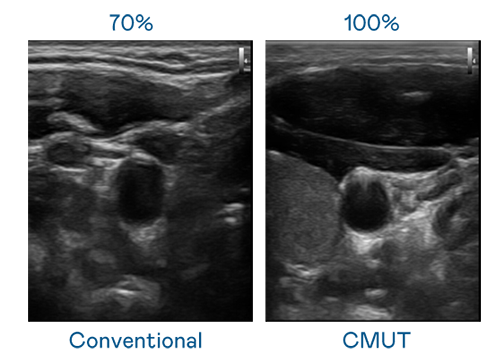

CMUT 技术是一种用电容式微机电元件来产生超音波讯号的技术。与传统 PZT 压电式技术相比,CMUT 频宽增加 30%,更宽频的超音波讯号让影像解析度大幅提升,是实现高影像品质医疗超音波扫描、促进精准医疗发展的关键技术。

大频宽带来超清晰影像

超音波影像的解析度高低,首先取决于探头能发出的讯号频宽。一个人免费观看在线高清中文 CMUT 可提供高清晰的超音波讯号,提供高频宽、高灵敏度、影像纹理细节更高的超音波影像,协助医护人员缩短影像判读时间及利用精准的医疗影像进行诊断。